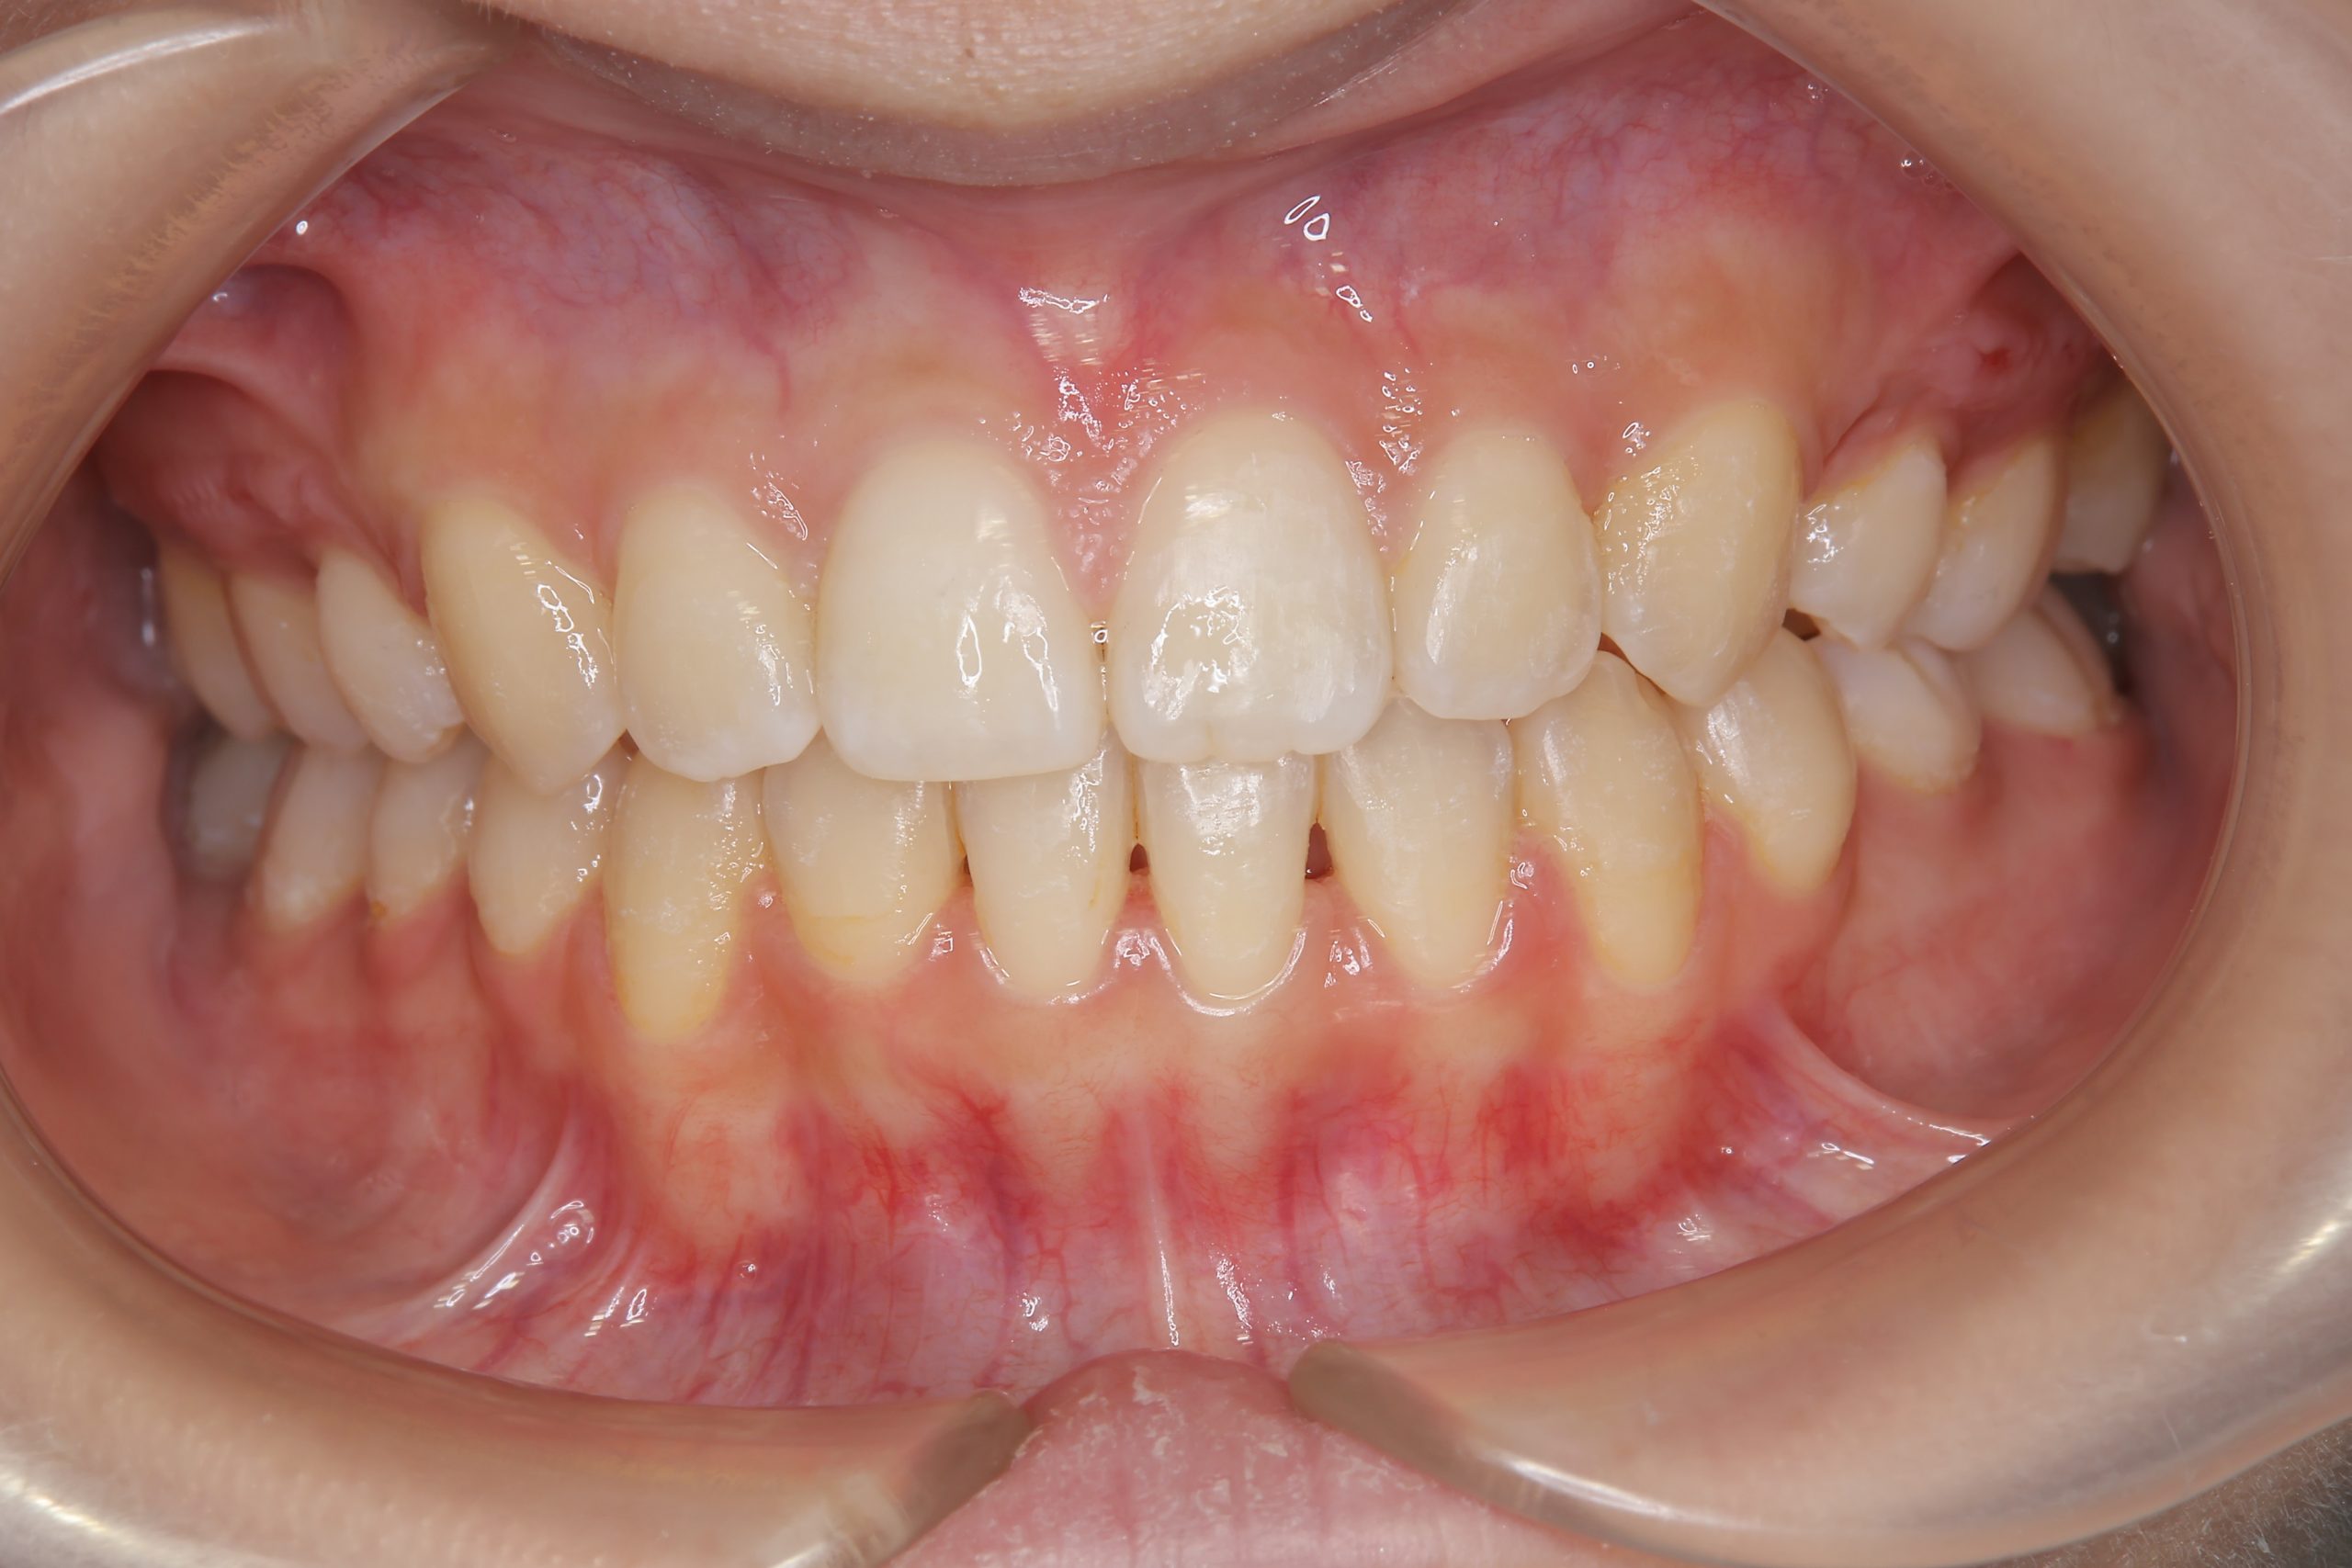

ビフォー

全顎ワイヤー矯正 症例_418

主訴 歯並びがガタガタ ※抜歯あり

施術内容 成人矯正1期治療

治癒期間 2年10か月間

費用 1,069,200円(税込)